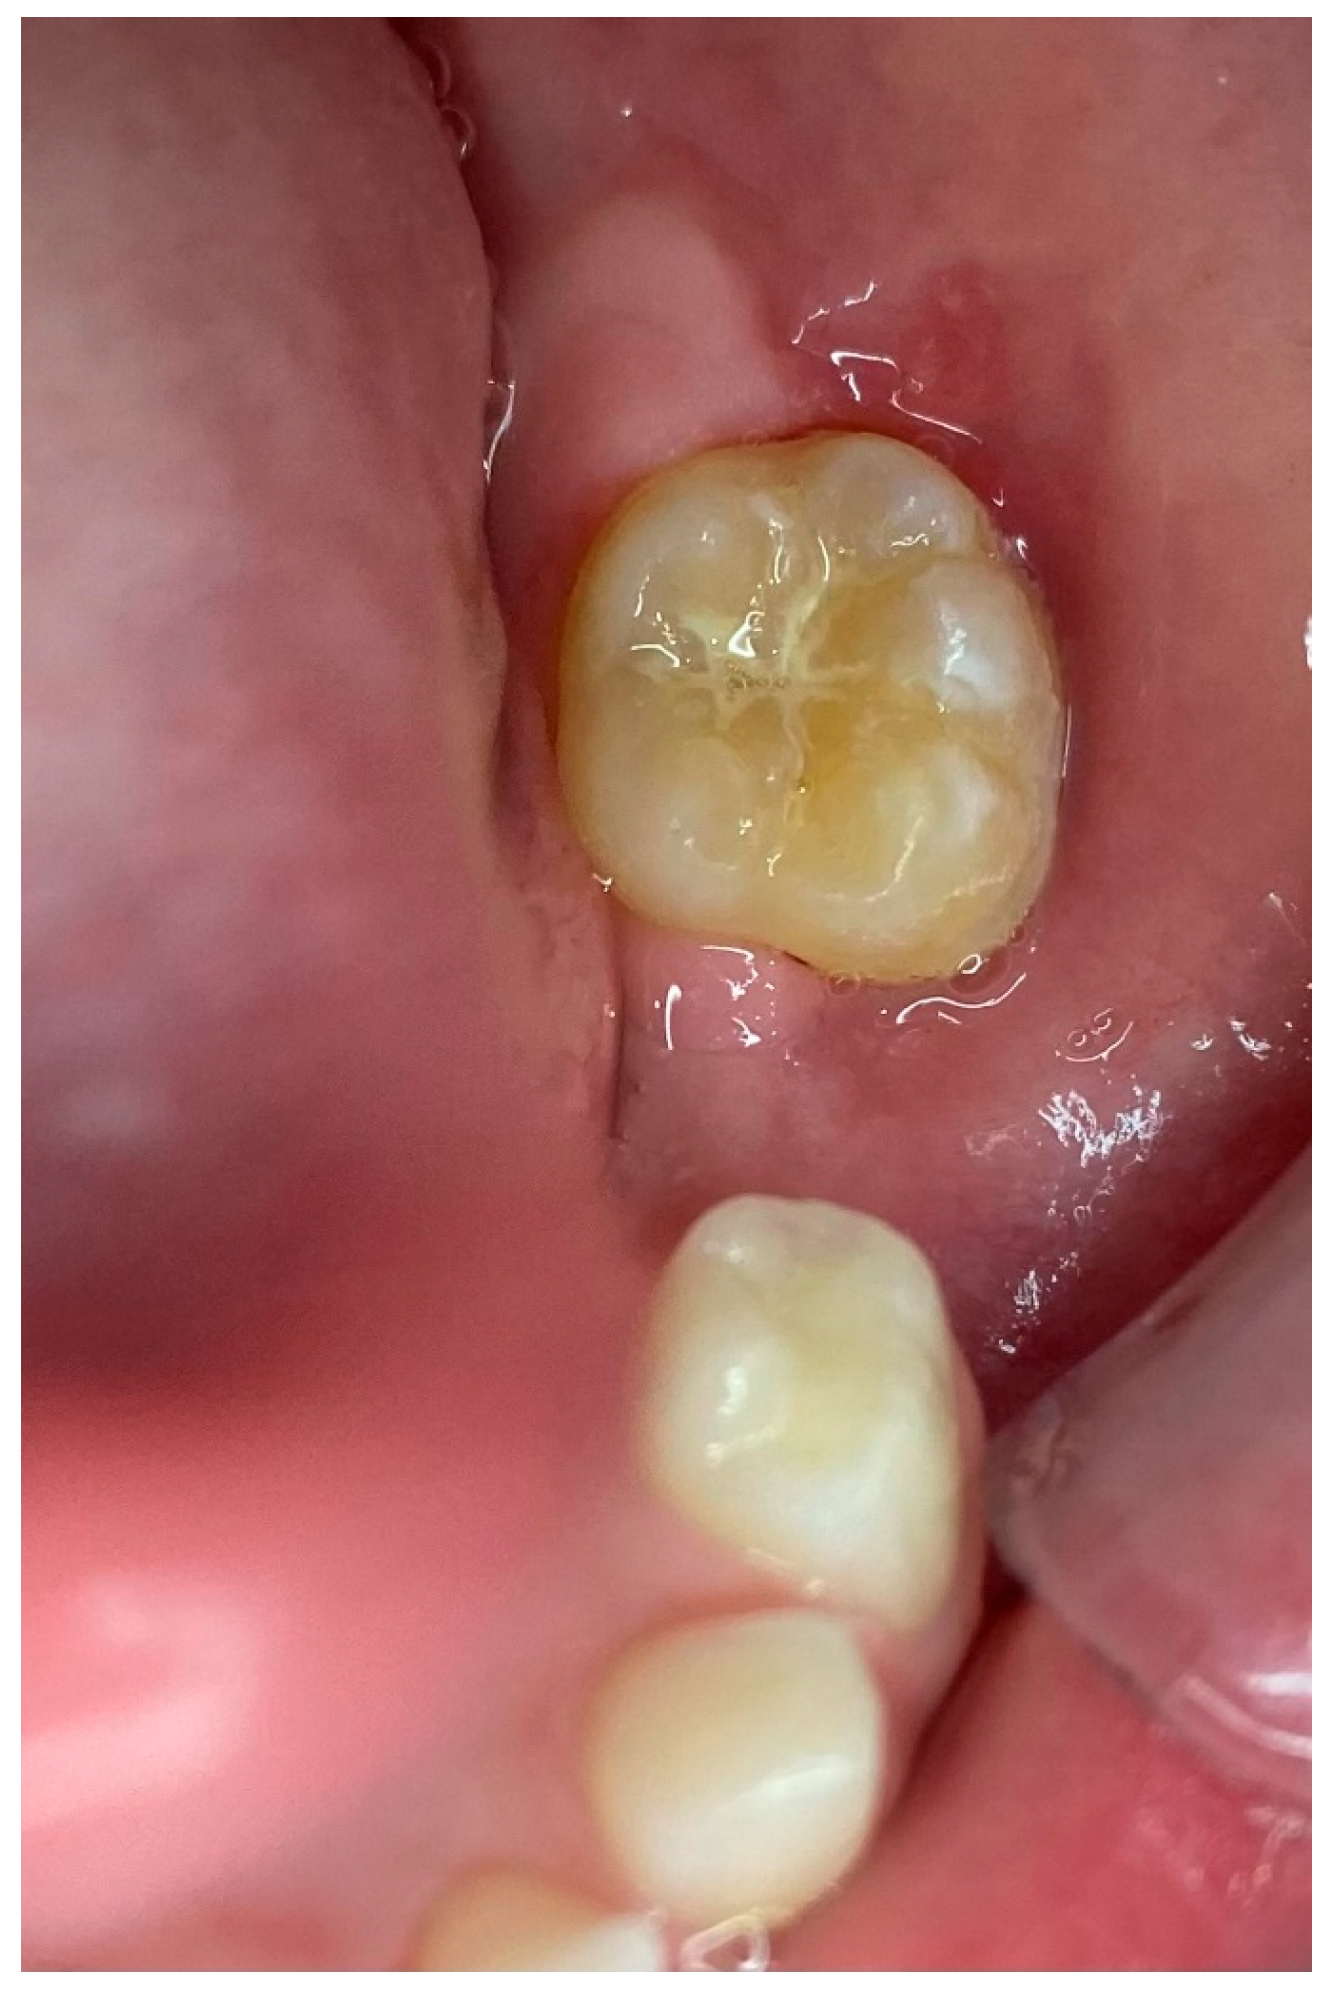

2. Case Presentation